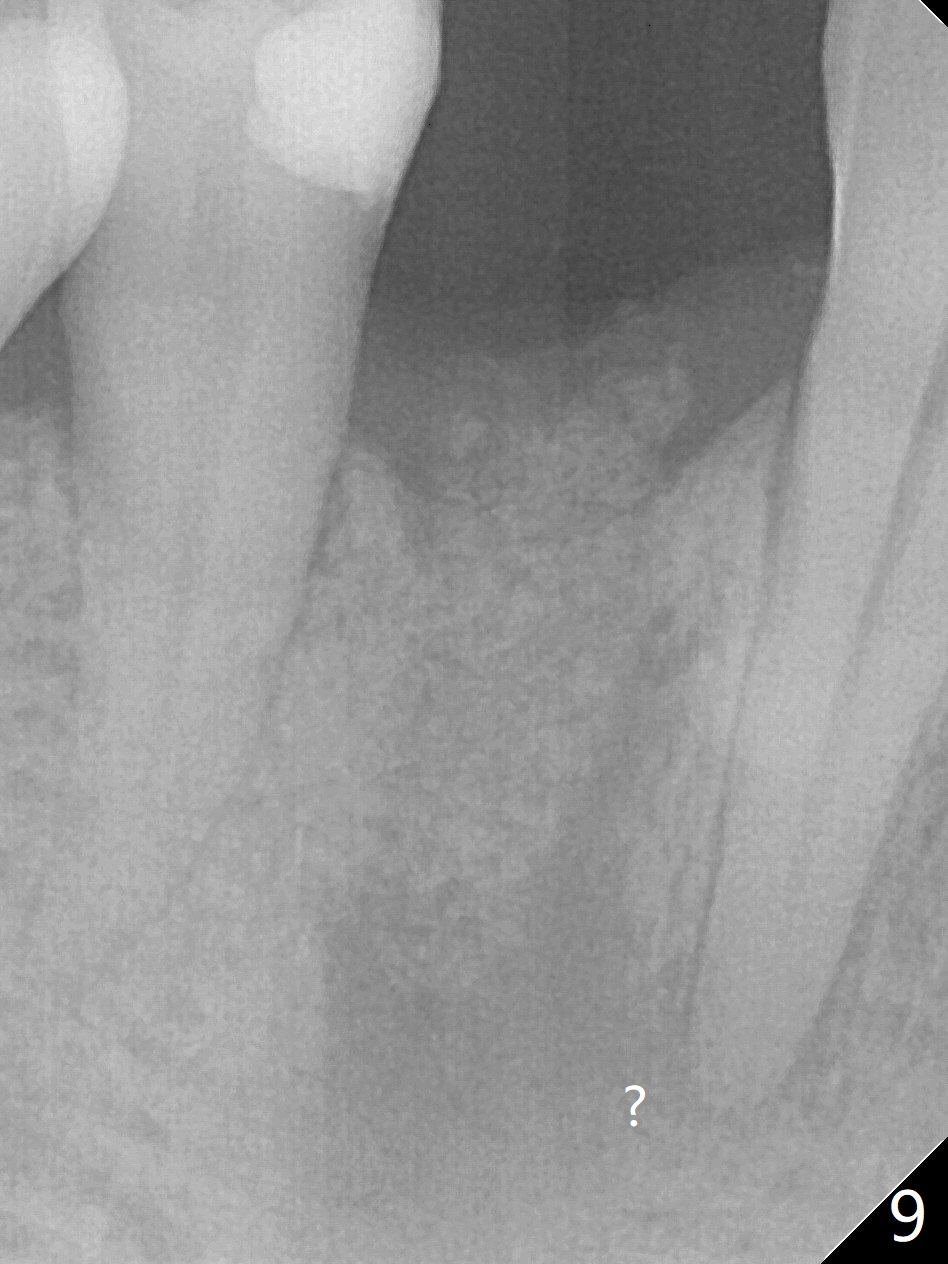

With 9 mm offset, the cylinder portion of the 2.2x8.5 mm drill does not engage to the metal sleeve of the guide at #28 after pointed drill (Fig.1). This issue could be solved with 12 mm offset, although it has no ill effect in this case. Fig.2 shows the site of #28 immediately before bone expansion and after use of 2.2x11.5 mm drill and small-scaled ridge split (^). The bone is so hard that the bone expansion is minimal (Fig.5) with autogenous bone graft and implant placement (Fig.4). There is the bone buccal to the implant clinically. A 5x10 mm implant is placed at #31 in the same appointment (Fig.3). Because of inability to masticate on the left (#18 root fracture with infection), the patient wants to restore #28 and 31 implants 3 months postop (Fig.6,7). The implant at #28 is removed while the healing abutment is being un-torqued without noting bone loss mesially (Fig.7 * (next similar case)). Bone graft is placed (Fig.8 (*),9). Pay attention radiolucency next the apex of the neighboring tooth (Fig.9 ?) before re-placement of an implant. The patient is upset, since he cannot eat. Two weeks later, a 6.5x4(4) mm cemented abutment is placed with 25 Ncm at #31 with a provisional for progressive loading for 2 weeks. Impression is taken. Two weeks later, a permanent crown is cemented without removing the underlying abutment. Two days later, the crown/abutment dislodges; a 6.8x6 mm healing abutment is placed. Eight days, it is difficult to reseat the existing crown and abutment. The mesiodistal edentulous space is limited as well. A 5.2x4(4) mm cemented abutment is able to be seated and torqued (30 Ncm) smoothly; in fact the clearance from the crestal bone (Fig.10 *) is not ample. If the abutment screw becomes loose in function, a profile drill should be used or a 4.5 mm in diameter abutment be placed. The abutment seems to remain in place immediate post cementation (Fig.11). Implant failure is probably due to no socket preservation (buccal plate atrophy) and too early restoration.